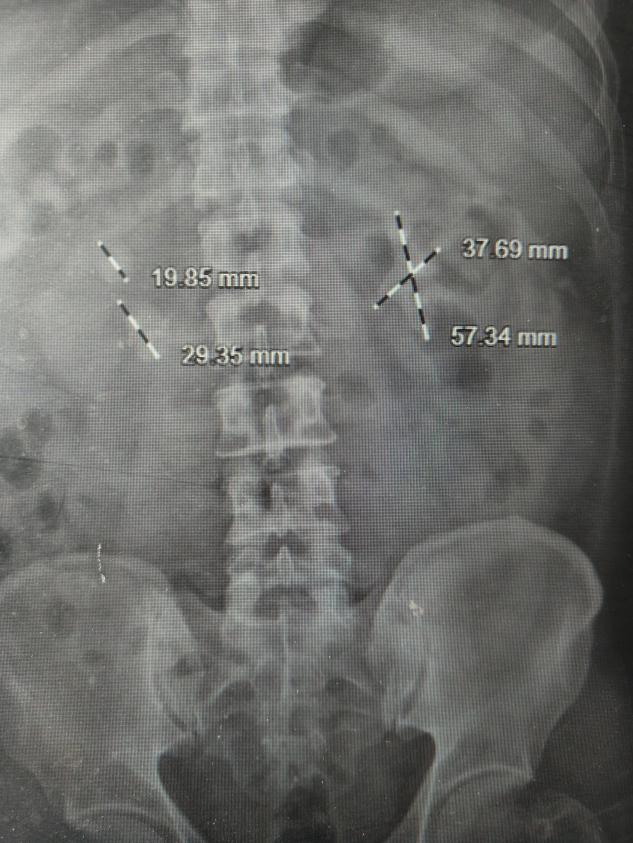

许多年前的一次体检,朱先生得知自己患有双肾结石。因当时症状不明显,也未规律复查。时间一晃而过。近期,朱先生时常感到腰部隐隐酸胀,体力也大不如前。他原以为是年纪大了的正常现象,直到一次剧烈的腰痛发作,才在家人的催促下就医,检查结果让他和家人都大吃一惊。CT显示,他的双肾结石,其中左肾几乎填满了各个肾盏,合并积水及感染,并且明确糖尿病,血糖超高。

“就像一个模具里灌满了石膏,结石完全依照肾脏内部的空腔形状生长,处理起来非常棘手。”泌尿外科主任、副主任医师刘伟光介绍,“尤其朱先生还有糖尿病,这大大增加了手术的复杂性和感染风险。”

· 第一步:攻坚右肾(存在积水的首先处理)。 在超声精确定位下,泌尿外科团队建立了仅铅笔粗细的微通道,利用高效的碎石设备,将右肾内坚硬的“石头城堡”逐步击碎、取出。手术顺利,手术后恢复良好。

· 第二步:清理左肾。 待右肾稳定恢复后,泌尿外科团队为左肾实施了取石手术。左侧结石更巨大、更复杂,手术团队凭借丰富的经验,再次成功完成“清剿”。

术后复查影像显示,朱先生的双侧肾脏结石已完全取净,肾积水消失。困扰朱先生多年的“石头包袱”,终于被彻底卸下。